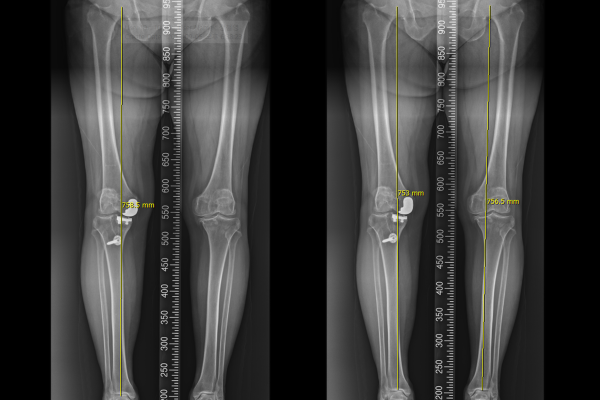

6c762d0732f22ffa67d913492363433d_1766047133_4588.png

수술실에서 제거한 기존 인공관절을 확인해보면 안쪽의 인공 물렁뼈(인공 연골판)이 닳아서 부러져 있는 것이 확인 되는데, 부러진 조각들이 무릎 안을 돌아다니며 무릎 통증 및 불편감을 일으킨 것으로 보입니다.